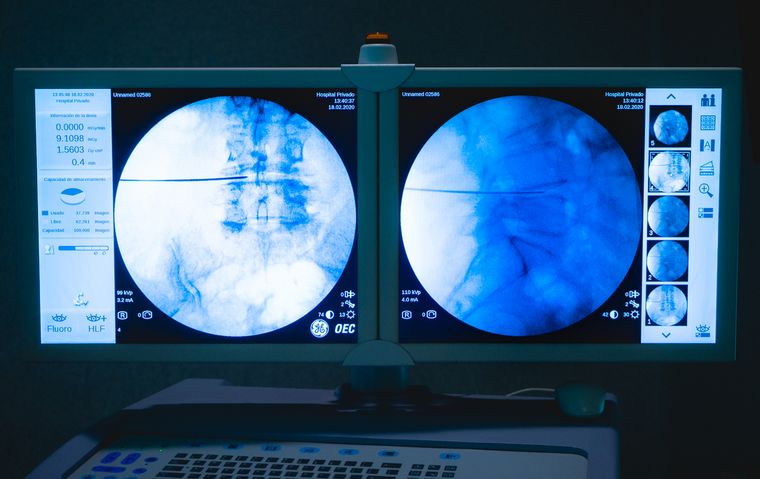

La utilización de las técnicas MISS en un centro médico depende de muchas variables institucionales, como son la tecnología y el instrumental disponible. Particularmente, Hospital Privado cuenta con aparatos de radioscopia de última generación, sistemas de navegación y técnicos en imágenes, especializados en la patología raquimedular.

La razón de la necesidad absoluta de contar con estas herramientas es que la minimización de una ruta de acceso conduce inevitablemente a una visualización más limitada del campo quirúrgico, o a ninguna visualización en absoluto. Por lo tanto, prevalece el uso de imágenes de rayos X para la orientación local, ya que los puntos de referencia anatómicos visuales que alguna vez fueron familiares en condiciones macroquirúrgicas pueden ser indistinguibles u oscurecidos. En algunos casos intraoperatoriamente es necesario utilizar sistemas de navegación para verificación del "área objetivo" de manera segura.